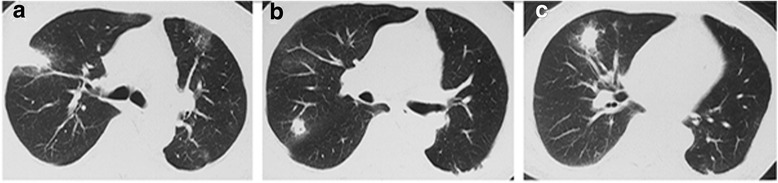

Fig. 1.

Pulmonary CT scan revealing multiple nodules in bilateral lung, including right upper lobe (a and b) and right middle lobe (c), which proved recurrence of lung cancer later by biopsy. (2016-3-21)